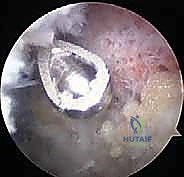

يقوم الدكتور هطيف بعمل 2 إلى 3 ثقوب صغيرة جداً حول الكتف. يتم إدخال كاميرا المنظار الدقيقة (بحجم القلم) من أحد الثقوب، وتُعرض الصورة مكبرة وعالية الدقة (4K) على شاشة أمام الجراح. يتم ضخ سائل معقم لتوسيع المفصل وتوضيح الرؤية وتقليل النزيف.

3. استكشاف المفصل وإزالة الأنسجة الملتهبة (Diagnostic Arthroscopy & Bursectomy):

قبل الوصول للترقوة، يقوم الجراح بفحص شامل لمفصل الكتف الداخلي (Glenohumeral joint) والحيز تحت الأخرم (Subacromial space). يتم استخدام جهاز الكي الحراري (Radiofrequency wand) لإزالة الجراب الملتهب (Bursa) والأنسجة الليفية المتندبة التي تسبب الألم.

4. الاستئصال العظمي الدقيق (Bone Resection - The Mumford Procedure):

هنا تتجلى خبرة الجراح. الهدف هو إزالة جزء صغير جداً من نهاية عظم الترقوة (الطرف البعيد).

* يتم استخدام أداة قطع عظمية دقيقة جداً (Arthroscopic Burr).

* الكمية المستأصلة حاسمة: يقوم الدكتور هطيف بإزالة حوالي 5 إلى 8 ملليمترات فقط من العظم. إزالة كمية أقل قد لا تحل مشكلة الاحتكاك، وإزالة كمية أكبر (أكثر من 10 ملم) قد تؤدي إلى عدم استقرار المفصل وتضرر الأربطة الغرابية الترقوية (CC ligaments) الحيوية. الدقة هنا تقاس بالملليمتر.

* يتم تشكيل نهاية العظم المتبقية لتكون ناعمة ومسطحة، مع التأكد من إزالة جميع النتوءات العظمية العلوية والخلفية لمنع أي احتكاك مستقبلي.

5. التقييم الديناميكي والإغلاق:

بينما لا يزال المريض تحت التخدير، يقوم الدكتور هطيف بتحريك ذراع المريض في جميع الاتجاهات (خاصة حركة التقريب المتقاطع) وهو يراقب المفصل عبر الشاشة للتأكد من وجود مسافة كافية بين الترقوة والأخرم (حوالي 1 سم) وعدم وجود أي اصطدام أو احتكاك عظمي متبقي.